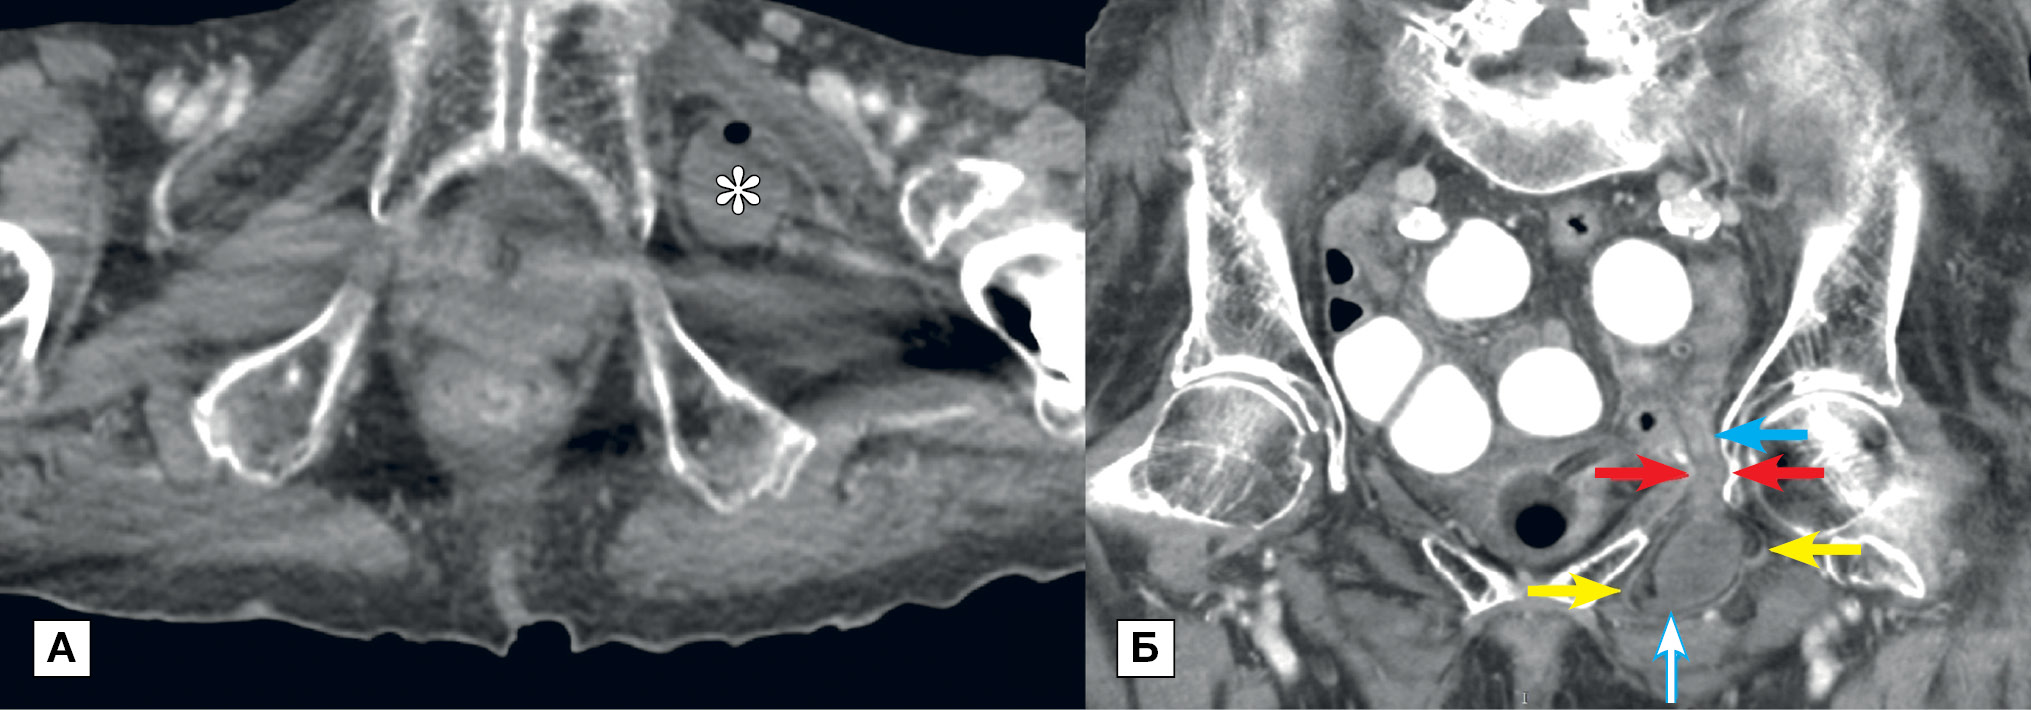

КТ пациентке была проведена через 27 ч с момента поступления в стационар и через 1 ч после приема воды с водорастворимым неионным контрастным препаратом в объеме 1,5 л. На полученных изображениях отмечались признаки тонкокишечной непроходимости с дилатацией петель тонкой кишки максимально до 36 мм на всем протяжении до уровня левого запирательного отверстия. Отмечалось проникновение петли подвздошной кишки через глубокое (тазовое) отверстие в запирательный канал с формированием на медиальной поверхности бедра под приводящими мышцами грыжевого мешка каплевидной формы размерами до 27×23×47 мм, содержащего петлю кишки протяженностью до 40 мм с наличием в ее просвете жидкостного содержимого и газа (рис. 1). Дистальнее грыжи — просвет тонкой кишки спавшийся. После контрастного усиления отмечалось снижение васкуляризации стенки кишки в грыжевом мешке вследствие ишемии. По результатам исследования было сформулировано следующее заключение: «КТ-признаки тонкокишечной непроходимости на фоне ущемленной левосторонней запирательной грыжи с признаками ишемии петли тонкой кишки в грыжевом мешке».

Рис. 1. Компьютерная томография органов брюшной полости и малого таза с пероральным и внутривенным болюсным контрастным усилением в венозную фазу контрастирования

Примечание. А — аксиальная проекция: грыжевой мешок (обозначен звездочкой), содержащий петлю тонкой кишки с жидкостным содержимым и пузырьком газа; Б — фронтальная проекция: проксимальнее запирательной грыжи визуализируются расширенные, заполненные контрастным препаратом петли тонкой кишки. Грыжевые ворота (красные стрелки). Наружные границы грыжевого мешка (желтые стрелки). Разница в васкуляризации стенки между неизмененной кишкой у входа в запирательный канал (голубая стрелка) и некротизированной петлей в грыжевом мешке (голубая полая стрелка).